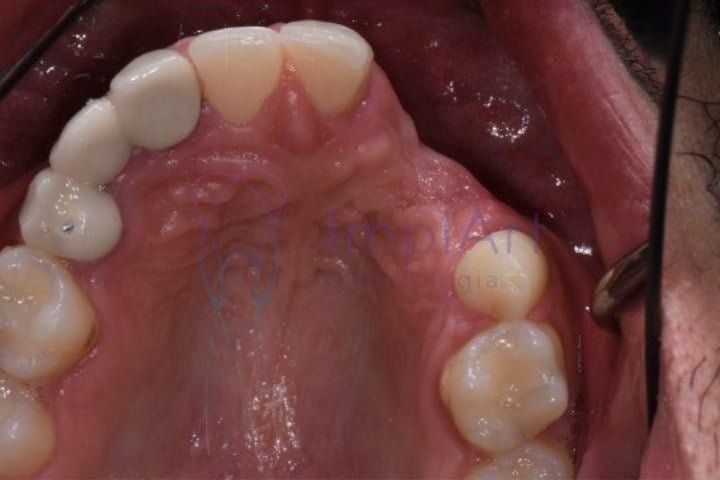

Quais as consequências da perda dos dentes? O que acontece na boca ao perder um dente? Por mais simples que pareça, a perda dos dentes que não são repostos imediatamente com implante dentário pode trazer consequências para a saúde e funcionalidade bucal no futuro, principalmente porque ocorre perda óssea. Com a ausência dental, a tendência é que os dentes próximos sofram movimentações, e os da arcada oposta podem sofrer com perda óssea. Portanto, a melhor alternativa é repor um dente perdido com implante dentario, o mais breve possível.

O tecido ósseo perde volume na altura e na espessura e essa descompensação pode gerar um desequilíbrio que afeta principalmente os dentes vizinhos. A deformidade óssea pode fazer que com os dentes remanescentes entortem ou girem.

A ausência de um dente pode fazer com que seu dente oposto se movimente. Por exemplo: uma pessoa perde um dente inferior e não repõe, o dente de cima, que até então fazia contato com o inferior tende a “descer”.

Também devemos considerar que, com a movimentação dos dentes vizinhos pela perda dos dentes, pode ser necessário reposicionar os dentes antes da inserção do implante. Como forma de recolocá-los em suas posições originais, e assim abrir o espaço que antes era ocupado pelo dente, podem ser utilizados aparelhos ortodônticos. Nestes casos, o tratamento ortodôntico aparece como coadjuvante do tratamento com implante dentario.